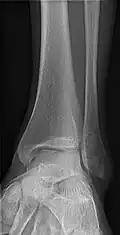

AP and lateral elbow X-ray

• Elbow - AP and Lateral. Radial head projections available on request

• Ankle - AP/Mortice and Lateral